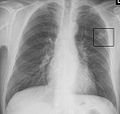

Nodules in skin include dermatofibroma[5] and pyogenic granuloma.[6] Nodules may form on tendons and muscles in response to injury,[7] and are frequently found on vocal cords.[8] They may occur in organs such as the lung,[9] or thyroid,[10] or be a sign in other medical conditions such as rheumatoid arthritis.[11]

Often discovered unintentionally on a chest x-ray, a single nodule in the lung requires assessment to exclude cancer.[9]